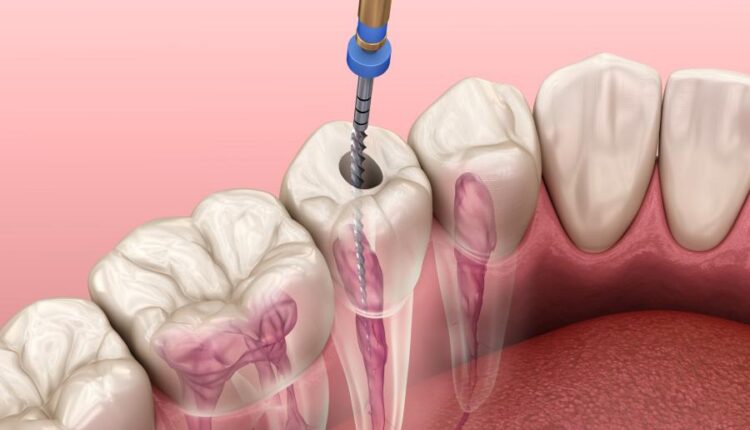

عکس استوک دندان و دندان پزشکی سه بعدی – Treatment of tooth 3d

مراکز و کلینیک های دندان پزشکی برای بردهایی که برای بیماران در محل قرار داده اند یک سری موارد تبلیغاتی و اینفوگرافیک طراحی می کنند که در آن مراحل درمان بیماران را با تصویر و اطلاعات کنار آن نشان می دهند. این تصاویر استوک دندان و دندان پزشکی سه بعدی بسیار می تواند برای طراحی این اینفوگرافیک ها مورد استفاده قرار گیرد.

نمونه عکس های استوک دندان و دندان پزشکی سه بعدی :